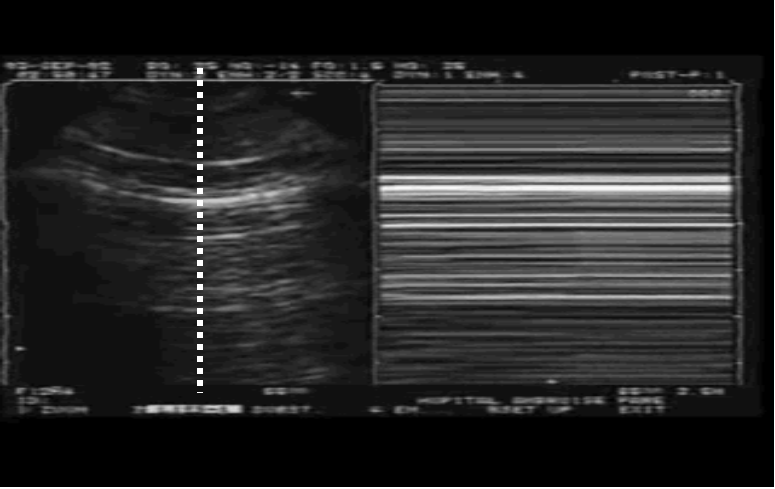

正常情况下,随着呼吸,双层胸膜之间有相对运动,通过超声可以看到肺滑动征。当发生气胸时,双层胸膜之间没有运动,只有胸壁在动,肺滑动征消失。

正常肺滑动征

气胸:肺滑动征消失

我们在M超放一个取样线,可以看到条码征(图9,也叫平流层征

图片